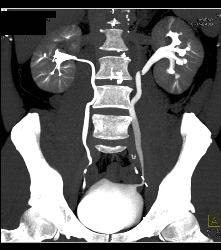

Diagnosis

Normal CT Urogram